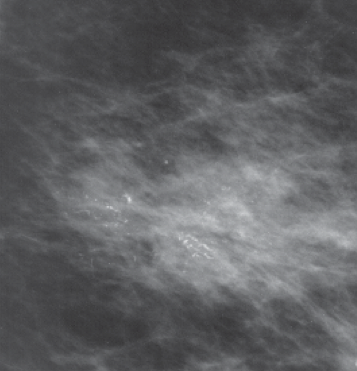

Clustered microcalcifications suggestive of low grade DCIS

DCIS is staged Tis. The clinical workup includes imaging studies. 95% of all DCIS is now found on screening mammograms. The mammographic presentation is generally a pattern of abnormal microcalcifications. Asymmetric densities make up about 10%, dominant masses another 8%. Suspicious calcifications are found in several moeieties: amorphous, coarse, pleomorphic and fine linear types. Linear and branching types are often found in higher grade DCIS and necrosis, whereas fine and granualr calcifications are more commonly seen in low grade DCIS.